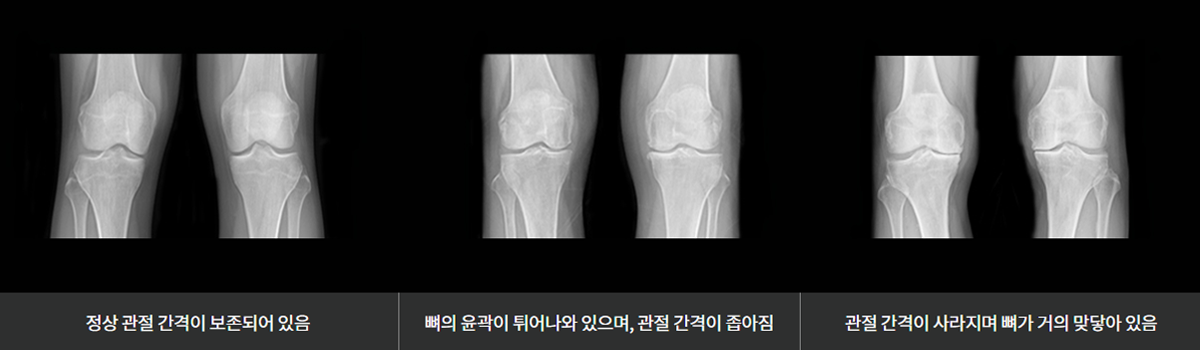

퇴행성 관절염은 관절 내의 정상적인 연골이 손상되거나 닳아 없어져서, 뼈와 뼈가 맞닿아서 발생하는 염증성 질환입니다.

주로 60세 전후의 나이에 발생하며, 특히 폐경기 이후의 여성에서 더 발생합니다. 고령, 외상, 비만, 변형 (내반슬 또는 외반슬),

염증 등의 원인에 의해 발생하며, 생활습관, 운동, 직업 등의 요인에 의해 악화할 수 있습니다. 질환이 진행되면 심한 통증 및

부종, 보행 장애, 운동 제한, 근육의 위축 등 증상이 발생하여 일상생활에 지장을 유발합니다.

연골 손상이 심하면 X-ray 검사에서 관절 간격이 감소하는 현상을 관찰할 수 있습니다.

의심되는 경우에는 MRI 검사를 시행하여 손상 부위 및 정도를 정확하게 판단할 수 있습니다.

초기의 손상은 MRI 검사로도 발견하기 어려우며, 관절내시경 상에서 정확한 연골 손상 정도를 확인할 수 있습니다.